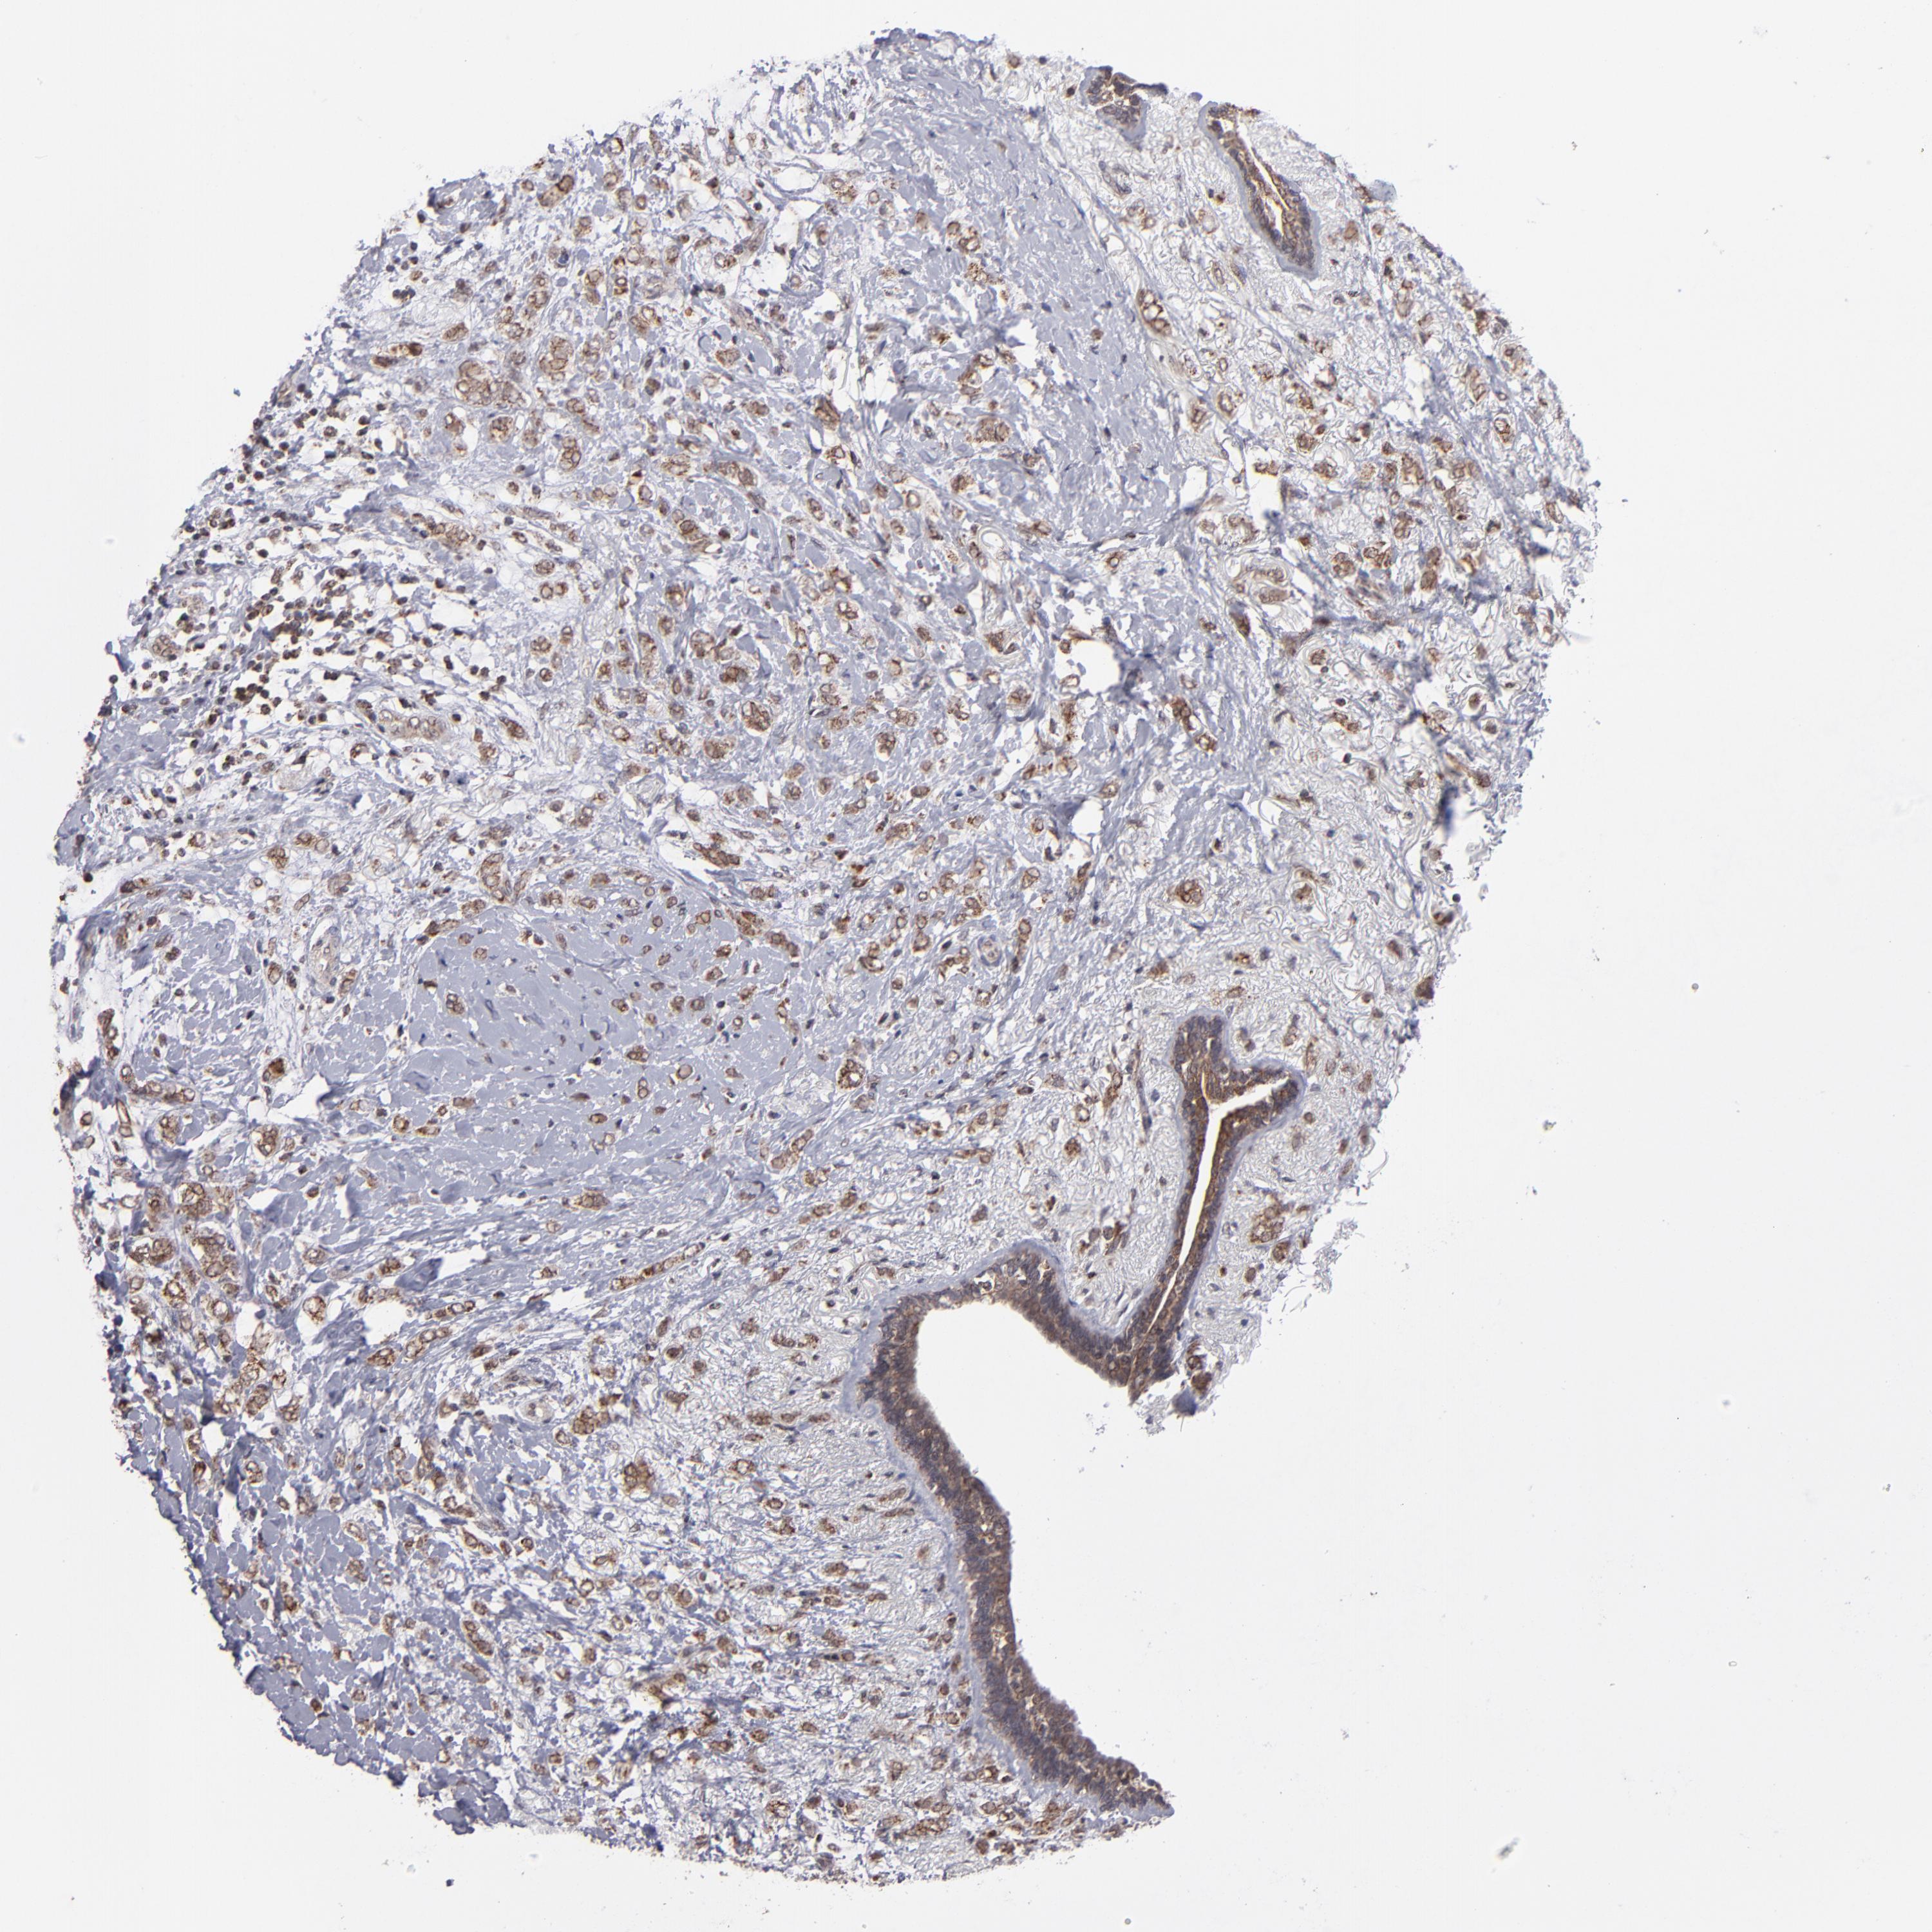

CANCER BREAST CANCER Show tissue menu

BRCA TCGA BRCA VALIDATION PROTEIN EXPRESSION